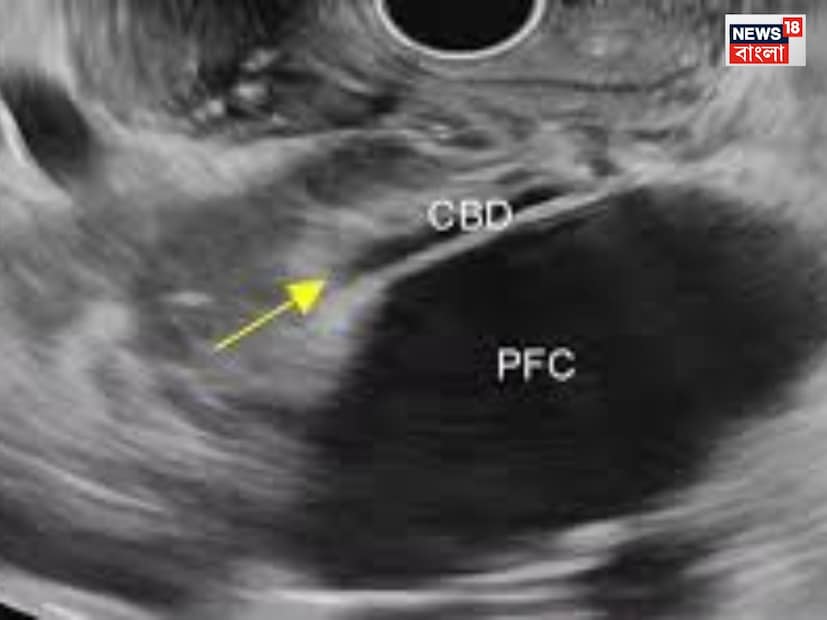

Hemorrhagic Pancreatitis: ময়নাতদন্তের প্রাথমিক রিপোর্টে চিকিৎসকরা বলছেন, অ্যাকিউট হেমরেজিক প্যানক্রিয়াটাইটিস ছিল তাঁর। এছাড়া ময়নাতদন্তে চিকিৎসকরা দেখেছেন, সৃঞ্জয়ের হার্টের আকার স্বাভাবিকের চেয়ে বেশি। কিডনি ও লিভারের আকারও স্বাভাবিকের চেয়ে বেশি ছিল।